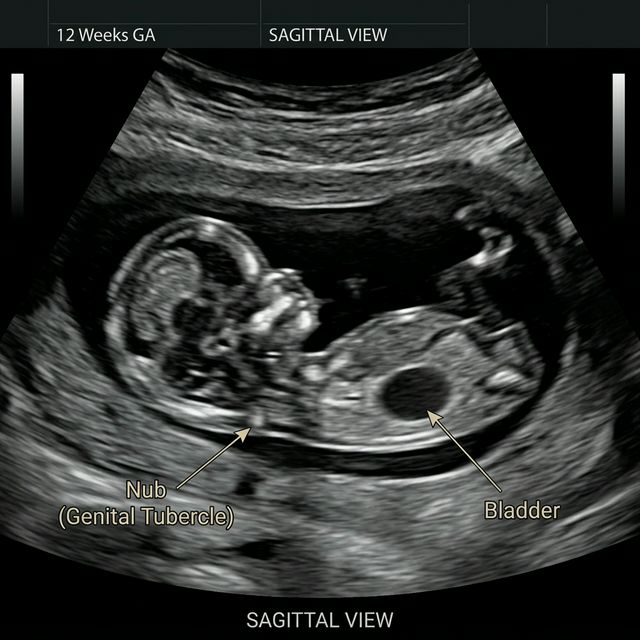

1. Upload or analyze your ultrasound image — use a clear side-profile (sagittal view) scan

2. Identify the baby's spine and nub — the spine appears as bright white dots, and the nub is a small protrusion near the base

Understanding nub theory boy vs girl differences becomes easier when you look at examples of nub angles in ultrasound images.

Nub theory ultrasound example showing boy vs girl nub angle differences at 11-13 weeks

Nub Theory: Girl nub angle (<30°) vs Boy nub angle (>30°) at 11–13 weeks

Why Bladder Position Matters in Nub Theory

The location of the fetal bladder relative to the nub provides additional confirmation:

• Boy prediction: Bladder typically appears below the nub.

• Girl prediction: Bladder is often seen above or level with the nub.

This occurs because male genital development shifts structures downward earlier than in females. When combined with nub angle, bladder position can improve prediction confidence—especially in borderline cases near 30°.

Nub Theory Bladder Position Explained

Did you know the position of the bladder plays a crucial role in nub theory accuracy? To correctly measure the angle of the genital tubercle (the 'nub'), ultrasound technicians use the lower spine and the bladder as reference points.